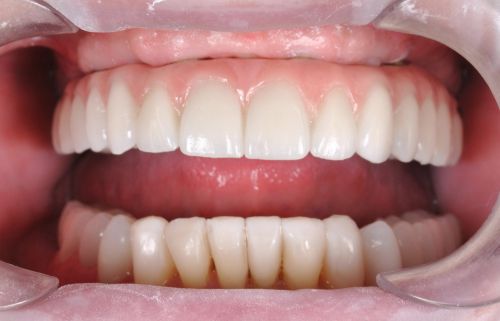

Wykonana praca protetyczna:

- most pełnołukowy na sześciu implantach

- korony na zęby własne w łuku dolnym

- korony na implantach w miejscach braków zębów

- odbudowa flow-injection zębów dolnych przednich